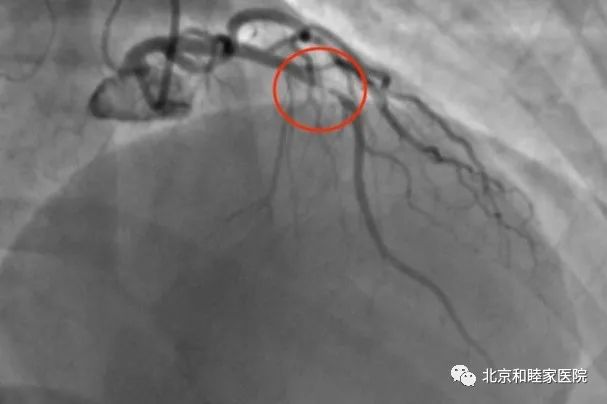

患者由救护车送到和睦家医院心脏中心,我们给患者做了冠脉造影检查,发现前降支(冠状动脉的一个最重要大分支)狭窄 99%,几乎闭塞。

心脏中心的介入团体研究后决定:只对病变部位进行 药物球囊扩张,并不植入支架,尽量保持患者血管的原始状态。

球囊扩张后的血管情况非常好,可以媲美支架植入。患者经过治疗后,后续会进行心脏康复训练,有望完全恢复到正常的工作和生活中去。